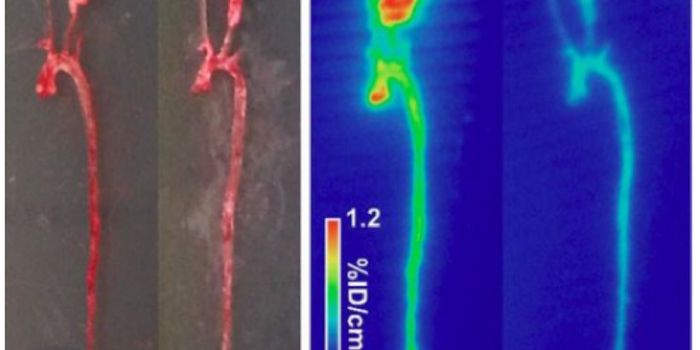

AUG 11, 2022Drug Discovery & DevelopmentIn a recent study published in Nature Medicine, a team of researchers from the Korea Advanced Institute of Science and T ...